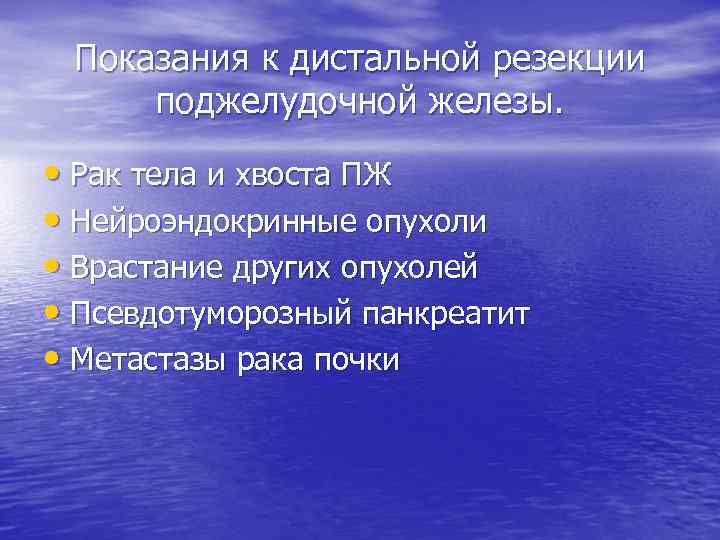

Показания к дистальной резекции поджелудочной железы. • Рак тела и хвоста ПЖ • Нейроэндокринные опухоли • Врастание других опухолей • Псевдотуморозный панкреатит • Метастазы рака почки